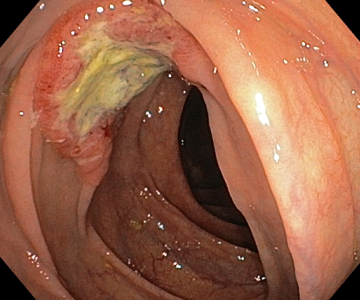

Пациент М, 40 лет. Беспокоили боли в брюшной полости. По ОАК -эозинофилия. Подготовка к колоноскопии идеальная, при исследовании выявили гельминта-аскариду, извлекли, аскарида была еще живая.

Пациент К, 75 лет, в 2018 году оперирован по поводу опухоли нисходящей ободочной кишки. Ежегодно проходил колоноскопии (не в нашей клинике), в июне 2024 года при обследовании в «Здоровье» выявили образование в восходящей ободочной кишке (от момента предыдущей колоноскопии (не у нас) полгода). Прооперирован.

Пациент О. 58 дет на протяжении нескольких лет наблюдалась по месту жительства с образованием желудка, по биопсии -гиперпластический полип. При обследовании в нашей клинике гистологически -тубулярная аденома с умеренной дисплазией и одним фрагментом тяжелой дисплазии (а это считается ранним раком), удален.

Пациент Ч 70 лет, ранний рак пищевода, направлен на лучевую терапию.